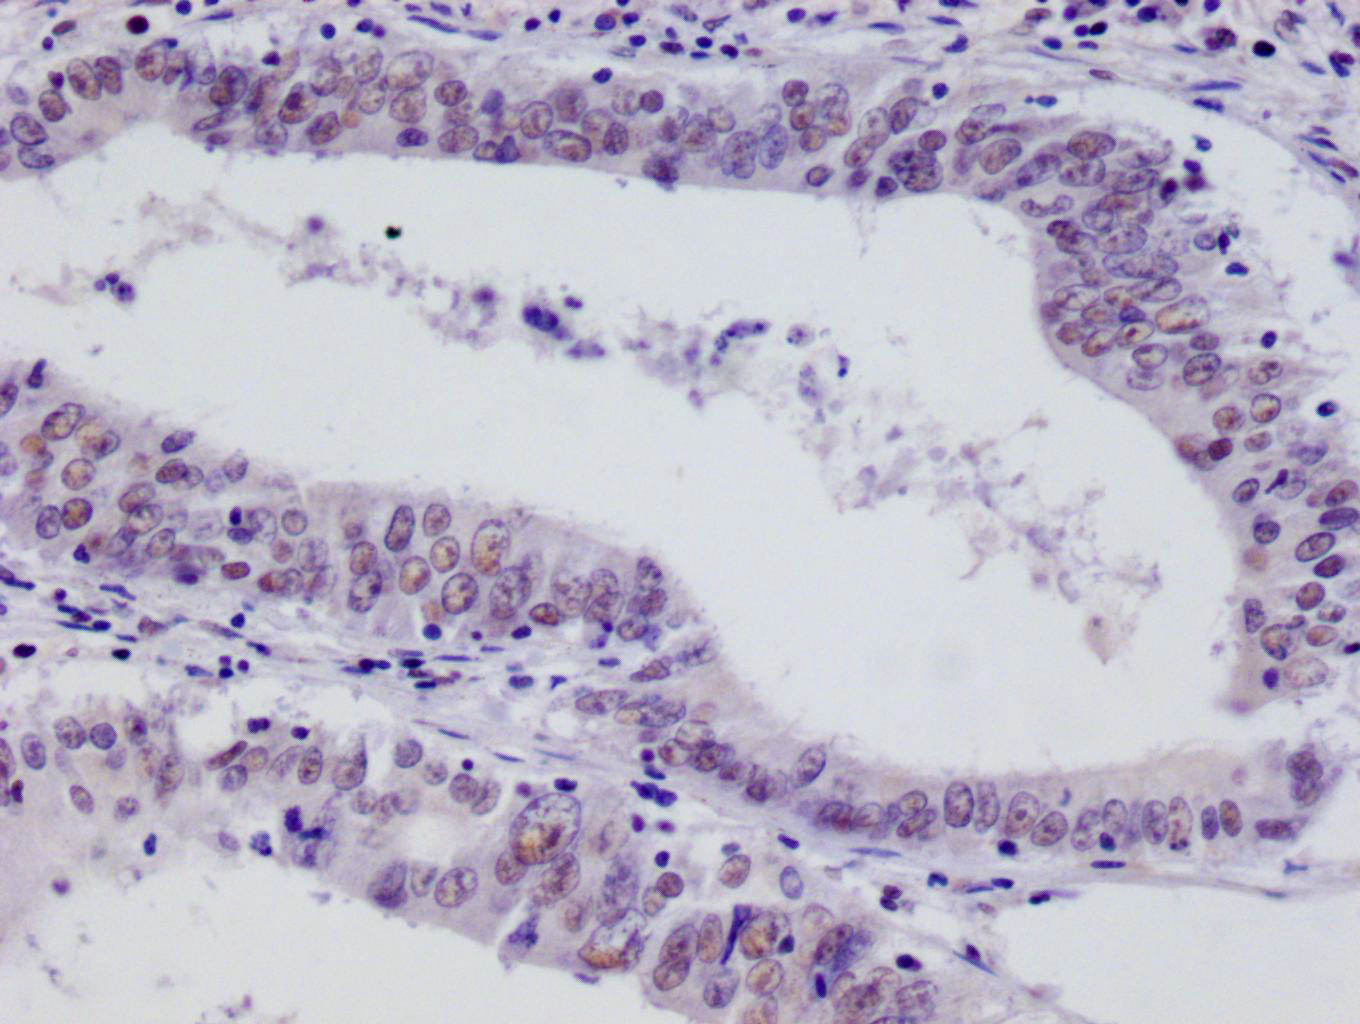

IHC image of CSB-RA256295A0HU diluted at 1:100 and staining in paraffin-embedded human testis tissue performed on a Leica BondTM system. After dewaxing and hydration, antigen retrieval was mediated by high pressure in a citrate buffer (pH 6.0). Section was blocked with 10% normal goat serum 30min at RT. Then primary antibody (1% BSA) was incubated at 4°C overnight. The primary is detected by a Goat anti-rabbit polymer IgG labeled by HRP and visualized using 0.05% DAB.